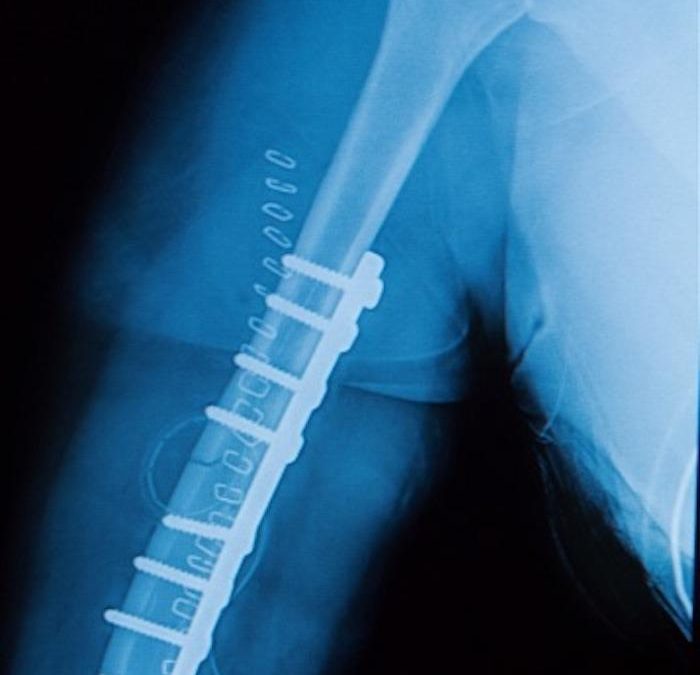

Stabilizing the Break: How Rods Help Fractures Heal Did you know that 6 million people break a bone every year in the United States? You can break any bone, but the most common fractures occur in the: Forearm Wrist Ankle Hip Shin Collarbone Spine But no matter which...